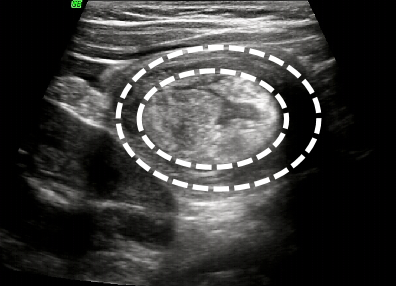

第二是“精准又快速”:肠套叠超声特征典型,“同心圆征”“套筒征”可明确识别;能精准定位套叠部位、范围,评估肠坏死、腹腔积液等并发症,为治疗提供依据。此外,超声检查操作便捷,通常10分钟可完成,能够快速明确诊断,为把握48小时“黄金治疗窗口期”提供有力支持,显著提升非手术复位成功率。